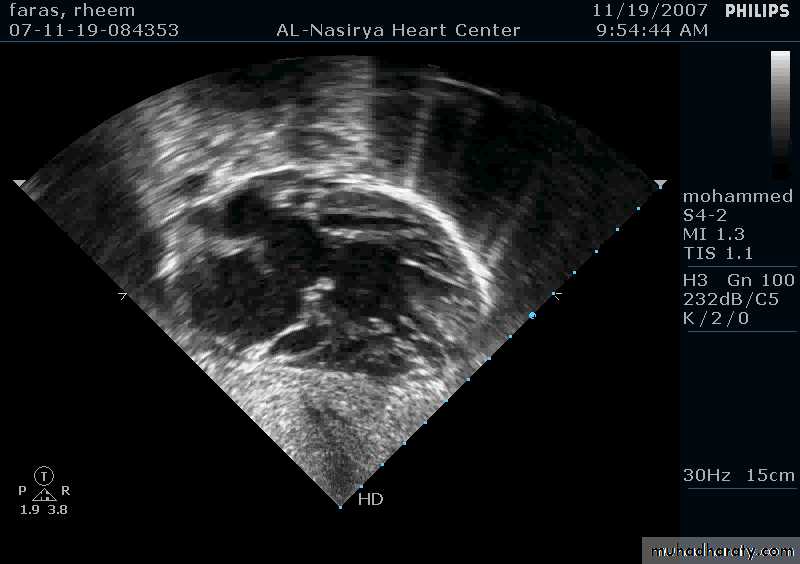

Ostium Primum ASD

37

38

33Echocardiography & TEE

Shows the size of the defectThe direction of blood flow

The pulmonary artery pressure34